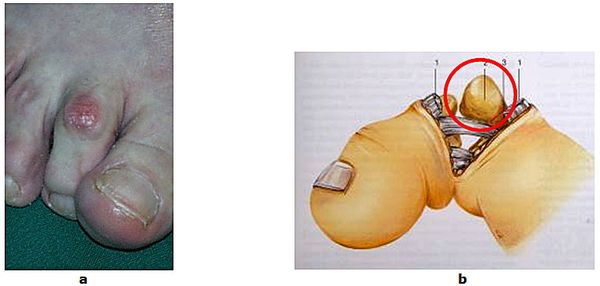

Abb.1: a Fortgeschrittene Hallux valgus Fehlstellung. Die Großzehe ist verdreht und verdrängt die zweite Zehe. Der Vorfuß ist verbreitert.

b Normaler Fuß

Abb.9: a Fixierte Krallenzehenfehlstellung mit Clavus (Hühnerauge).

b Der störende Knochen wird entfernt (Resektionsarthroplastik nach Hohmann)